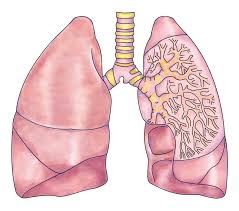

1. 폐암이란 무엇인가요?

폐암은 폐에 있는 세포가 비정상적으로 증식하는 질환으로, 크게 비소세포폐암과 소세포폐암으로 나뉩니다. 대부분은 비소세포폐암에 해당하며, 소세포폐암은 진행이 빠르고 전이가 잘 되는 특징이 있습니다.

폐는 산소와 이산화탄소를 교환하는 중요한 기관이므로, 암이 발생하면 호흡 기능에 치명적인 영향을 줍니다.